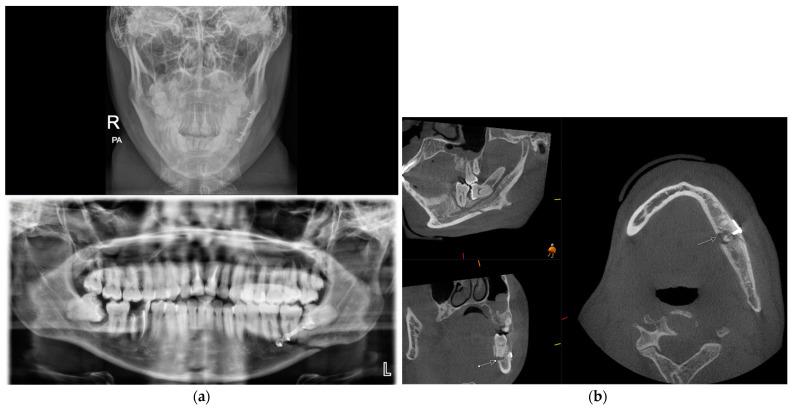

The assessment and management of facial trauma in an acute setting is one of the core services provided by oral and maxillofacial units in the United Kingdom. Imaging is a pre-requisite for appropriate diagnosis and treatment planning, with a combination of plain radiographs and medical-grade CT being the mainstay. However, the emergence of cone beam CT in recent years has led to its wider applications, including facial trauma assessment. It can offer multi-planar reformats and three-dimensional reconstruction at a much lower radiation dose and financial cost than conventional CT. The purpose of this review is to appraise its potential indications in all anatomical areas of maxillofacial trauma and provide our experience at a level 1 trauma centre.

在急性情况下对面部创伤进行评估和处理是英国口腔颌面科室提供的核心服务之一。影像学检查是进行恰当诊断和治疗规划的先决条件,主要依靠普通X光片和医用级CT的联合使用。然而,近年来锥形束CT的出现使其得到了更广泛的应用,包括面部创伤评估。与传统CT相比,它能够以更低的辐射剂量和经济成本提供多平面重建和三维重建。这篇综述的目的是评估其在颌面创伤所有解剖区域的潜在适应证,并介绍我们在一级创伤中心的经验。